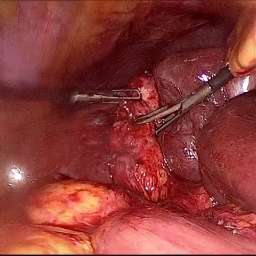

Refer to caption (a) Input Refer to caption (b) case1 Refer to caption (c) case2 Refer to caption (d) case3 Refer to caption (e) Ours Refer to caption (f) Target

Figure 4: Ablation comparisons sampled from the DesmokeData and LSD3K datasets. The first two rows are from DesmokeData and the last two rows are from LSD3K. (settings: case1 = ADA+CrossGating, case2 = DHA+CrossGating, case3 = DHA+ADA).

IV-D Ablation Studies

To validate the effectiveness and individual contributions of the core components of our proposed RGA-Net, we conducted a series of ablation experiments on the DesmokeData dataset. We systematically analyzed the impact of our key designs: the DHA module, the ADA module, and the Cross-Gating (CG) mechanism for feature fusion. In these studies, we created several variants of our network by removing or replacing one component at a time and evaluated their performance. The quantitative results of these experiments are presented in Table II, and qualitative visual comparisons are shown in Fig. 4.

IV-D1 Effectiveness of the Dual-Stream Hybrid Attention Module

The DHA module is designed to capture both local surgical details and global illumination changes by combining shifted window attention with a frequency-domain processing branch. To ablate its effect, we replaced the DHA modules in the encoder with standard Swin Transformer blocks, thus removing the spectral pathway and the hybrid attention mechanism. As demonstrated in Table II, this variant experienced a significant drop in performance. This decline highlights the importance of integrating frequency-domain information, which is crucial for handling the complex light scattering caused by surgical smoke and restoring high-frequency textural details. The results confirm that the dual-stream approach provides a richer feature representation than spatial attention alone.

IV-D2 Effectiveness of the Axis-Decomposed Attention Module

We then investigated the contribution of the ADA module, which is employed in the decoder and latent space to efficiently process multi-scale features. We created a variant where the ADA modules were substituted with a more conventional self-attention mechanism without the block and grid axis decomposition. The results in Table II show a clear degradation in performance for this variant compared to the full model. This outcome validates that factorizing attention along two distinct axes allows the model to capture both fine-grained local patterns and long-range spatial dependencies more effectively and efficiently. The ADA module’s design provides a powerful yet computationally manageable way to model complex feature relationships during the reconstruction phase.

IV-D3 Effectiveness of the Cross-Gating Mechanism

Finally, we analyzed the efficacy of the cross-gating mechanism used for multi-scale feature fusion between the encoder and decoder. We replaced our CG blocks with a standard skip-connection method, specifically simple concatenation followed by a convolutional layer, as is common in many U-Net-based architectures. As shown in Table II, this change resulted in a substantial performance decrease. This finding underscores the superiority of the bidirectional feature modulation offered by our CG mechanism. Unlike simple fusion, cross-gating allows the encoder and decoder pathways to selectively amplify relevant features and suppress irrelevant information from each other, leading to a more refined and effective integration of multi-scale context, which is vital for high-quality image reconstruction.

In conclusion, the ablation studies comprehensively demonstrate that each of our proposed components—DHA, ADA, and CG—is integral to the overall performance of RGA-Net. The full model consistently outperforms all ablated variants, proving the synergistic benefits of our architectural design for the challenging task of surgical smoke removal.